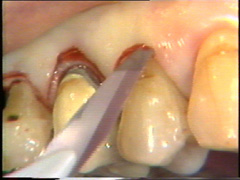

Incisiones en la cirugía periodontal

La incisión inicial se empieza alrededor de 10-15 mm distal del  último diente hasta la línea media del proceso alveolar. Esto se hace para evitar el cierre del colgajo  que está en la proximidad de la  furcación que se abre en distal del primer molar. La incisión se realiza con una presión tal para  llegar a hacer contacto con el hueso.

La incisión es entonces continuada en  bucal siguiendo la línea del margen gingival pero ubicando el corte en 1 a 1,5 mm hacia apical. La incisión debe partir de coronal del hueso alveolar en la  proximidad del diente. En el segundo premolar el bolsillo está muy profundo y aquí la incisión se ensancha para generar reducción de la bolsa  que luego es reemplazado por el colgajo.

La profundidad al sondaje en  los primeros premolares en bucal es poco profunda y aquí la incisión se ubica en el surco ginginval propiamente dicho. El escalpelo se mueve a través del tejido con un serrar suave y con pulso firme.

En bucal del canino la bolsa es poco profunda y aquí la incisión se ubica más cerca en de la gingiva del diente. En el lateral la insición se ubica más hacia apical de la superficie del diente.

La intención de este corte es separar los tejidos adyascentes del diente (sanos) del  tejido periodontal infectado (tejido de granulación, cemento infectado y cálculo)

En palatino debe usarse el mismo principio pero la diferencia radica que el tejido palatino es muy fibroso por lo tanto el corte puede realizarse más apical para eliminar la bolsa y poder adaptar mejor el colgajo, que por ser más fibroso es menos flexible que los colgajos bucales.